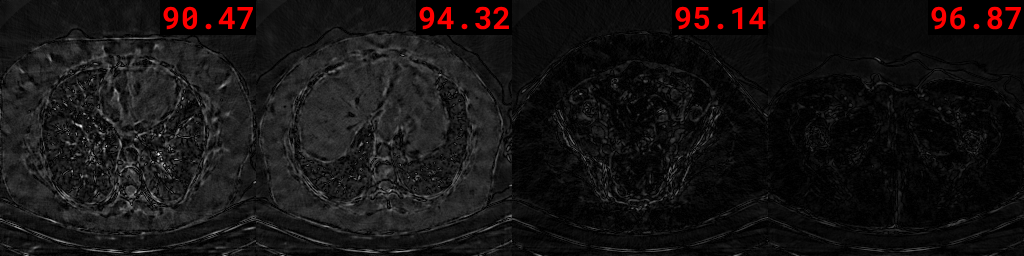

Figure 7: Visualization of the inverse Hessian approximation across iterations. Observe the subtle changes between each iteration, attributed to the influence of the objective function used to estimate Htsubscript𝐻𝑡H_{t} (see Eq. 10).

Refer to caption

Figure 7 depicts 𝑯tsubscript𝑯𝑡{\bm{H}}_{t} at different iterations. These visualizations confirm the required symmetry of the matrix in each iteration. Additionally, the matrix 𝑯tsubscript𝑯𝑡{\bm{H}}_{t} is close to the identity matrix at the second iteration, becoming more structured in the third iteration. This behavior aligns with expectations, as the matrix 𝑯tsubscript𝑯𝑡{\bm{H}}_{t} is initialized as the identity matrix and updated based on gradient information and solution changes.

Visualization of reshaped rows.

To further understand the inverse Hessian matrix approximation structure, we depict the reshaped (64×64646464\times 64) first 404040 rows of 𝑯tsubscript𝑯𝑡{\bm{H}}_{t} at iterations 999 and 141414 in Fig. 8. These rows store gradient attention information used for updating the solution, consistent with the matrix 𝑯tsubscript𝑯𝑡{\bm{H}}_{t} being updated based on gradient information and solution changes. In future work, we plan to explore the impact of 𝑯tsubscript𝑯𝑡{\bm{H}}_{t} on the optimization process and its influence on reconstruction performance.